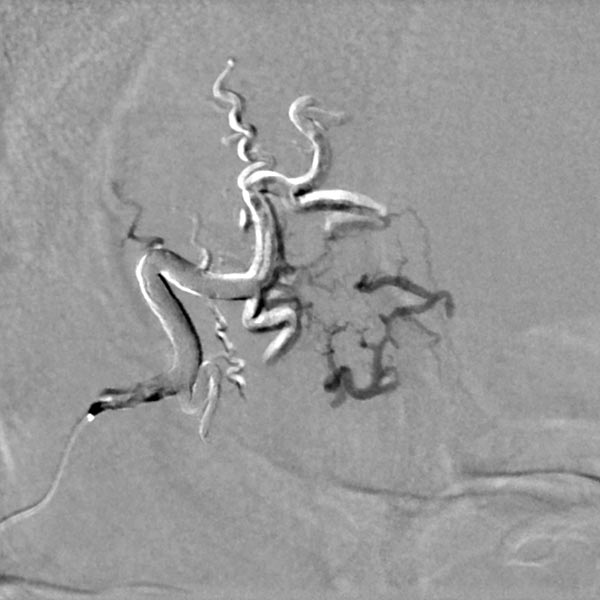

Nach superselektiver Sondierung über einen Mikrokatheter schrittweise Auffüllung des gesamten Nidus der AVM mittels Ethylen-Vinyl-Akohol-Kopolymer mit Hilfe der plug-und-push Technik, bei der die Katheterspitze eingeklebt wird und das Embolisat in die Läsion gedrückt wird. Darstellung in der hier folgenden Bilder in Roadmap-Technik, in der bereits injiziertes Embolisat weiß, neu hinzugekommenes Embolisat schwarz dargestellt wird. Beachte die zunehmende, retrograde Füllung der kleinen Feederarterie am unteren Rand der Läsion (Beginn der Injektion).

Beachte die zunehmende, retrograde Füllung der kleinen Feederarterie am unteren Rand der Läsion (während der Injektion).

Beachte die zunehmende, retrograde Füllung der kleinen Feederarterie am unteren Rand der Läsion (nach der Injektion). Die kleine Arterie wurde gegen ihre Stromrichtung aufgefüllt.